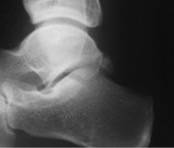

Os Trigone

Cette ossification (non systématique) au niveau de la partie postérieure du talus peut être traumatisée lors des mouvements d’hyper flexion plantaire de la cheville.

Le bilan d’imagerie doit être complet pour valider la lésion (radio, scanner et IRM).